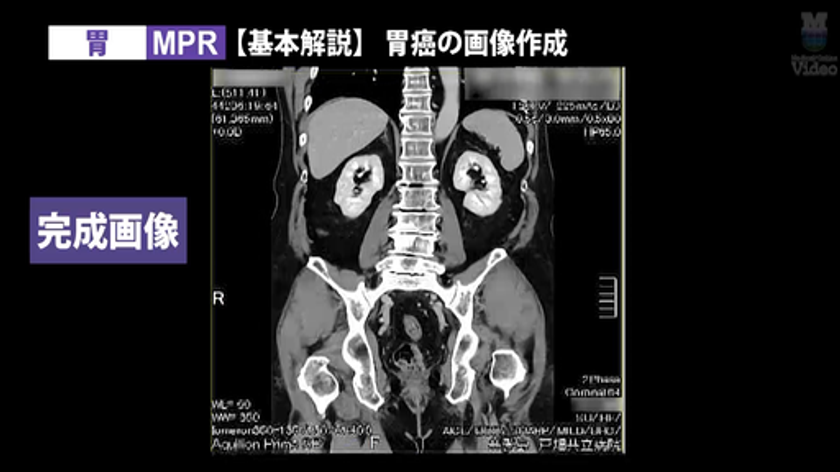

● 3D画像製作 胃 MPR・VR

画像5: https://www.atpress.ne.jp/releases/553365/LL_img_553365_5.png

3D画像製作 胃

https://video.medicalonline.jp/videos/826

3D画像作成の人気シリーズに、「胸郭出口症候群(TOS)」と「胃」の新作を追加。CT撮影から3D画像作成までの流れを、実際の画面キャプチャを交えて徹底解説します。

監修:山本 晃義先生(戸畑共立病院)/実演・解説:田原 琢朗先生

3D画像作成技術をさらに磨きたい放射線技師に向けた、実践的な内容です。